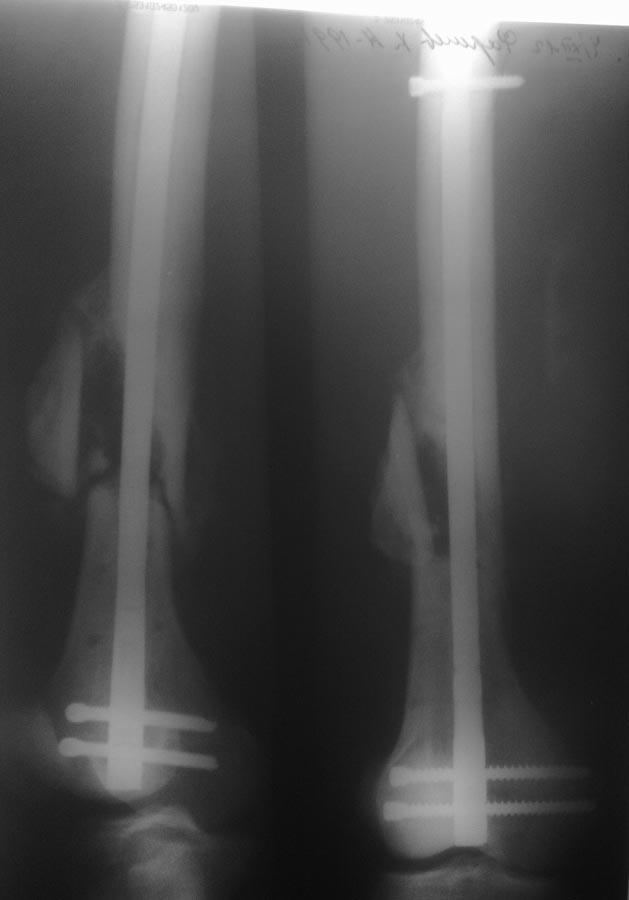

Всем спасибо! Что мы сделали: удалили прокссимальный фрагмент без проблем. Дистальный: через сустав рассверлен канал 13мм. до дистального фрагмента. Который затем удален через тот же канал при помоши загнутой спицы, без особых проблем. Далее ретроградный остеосинтез гвоздем №10.